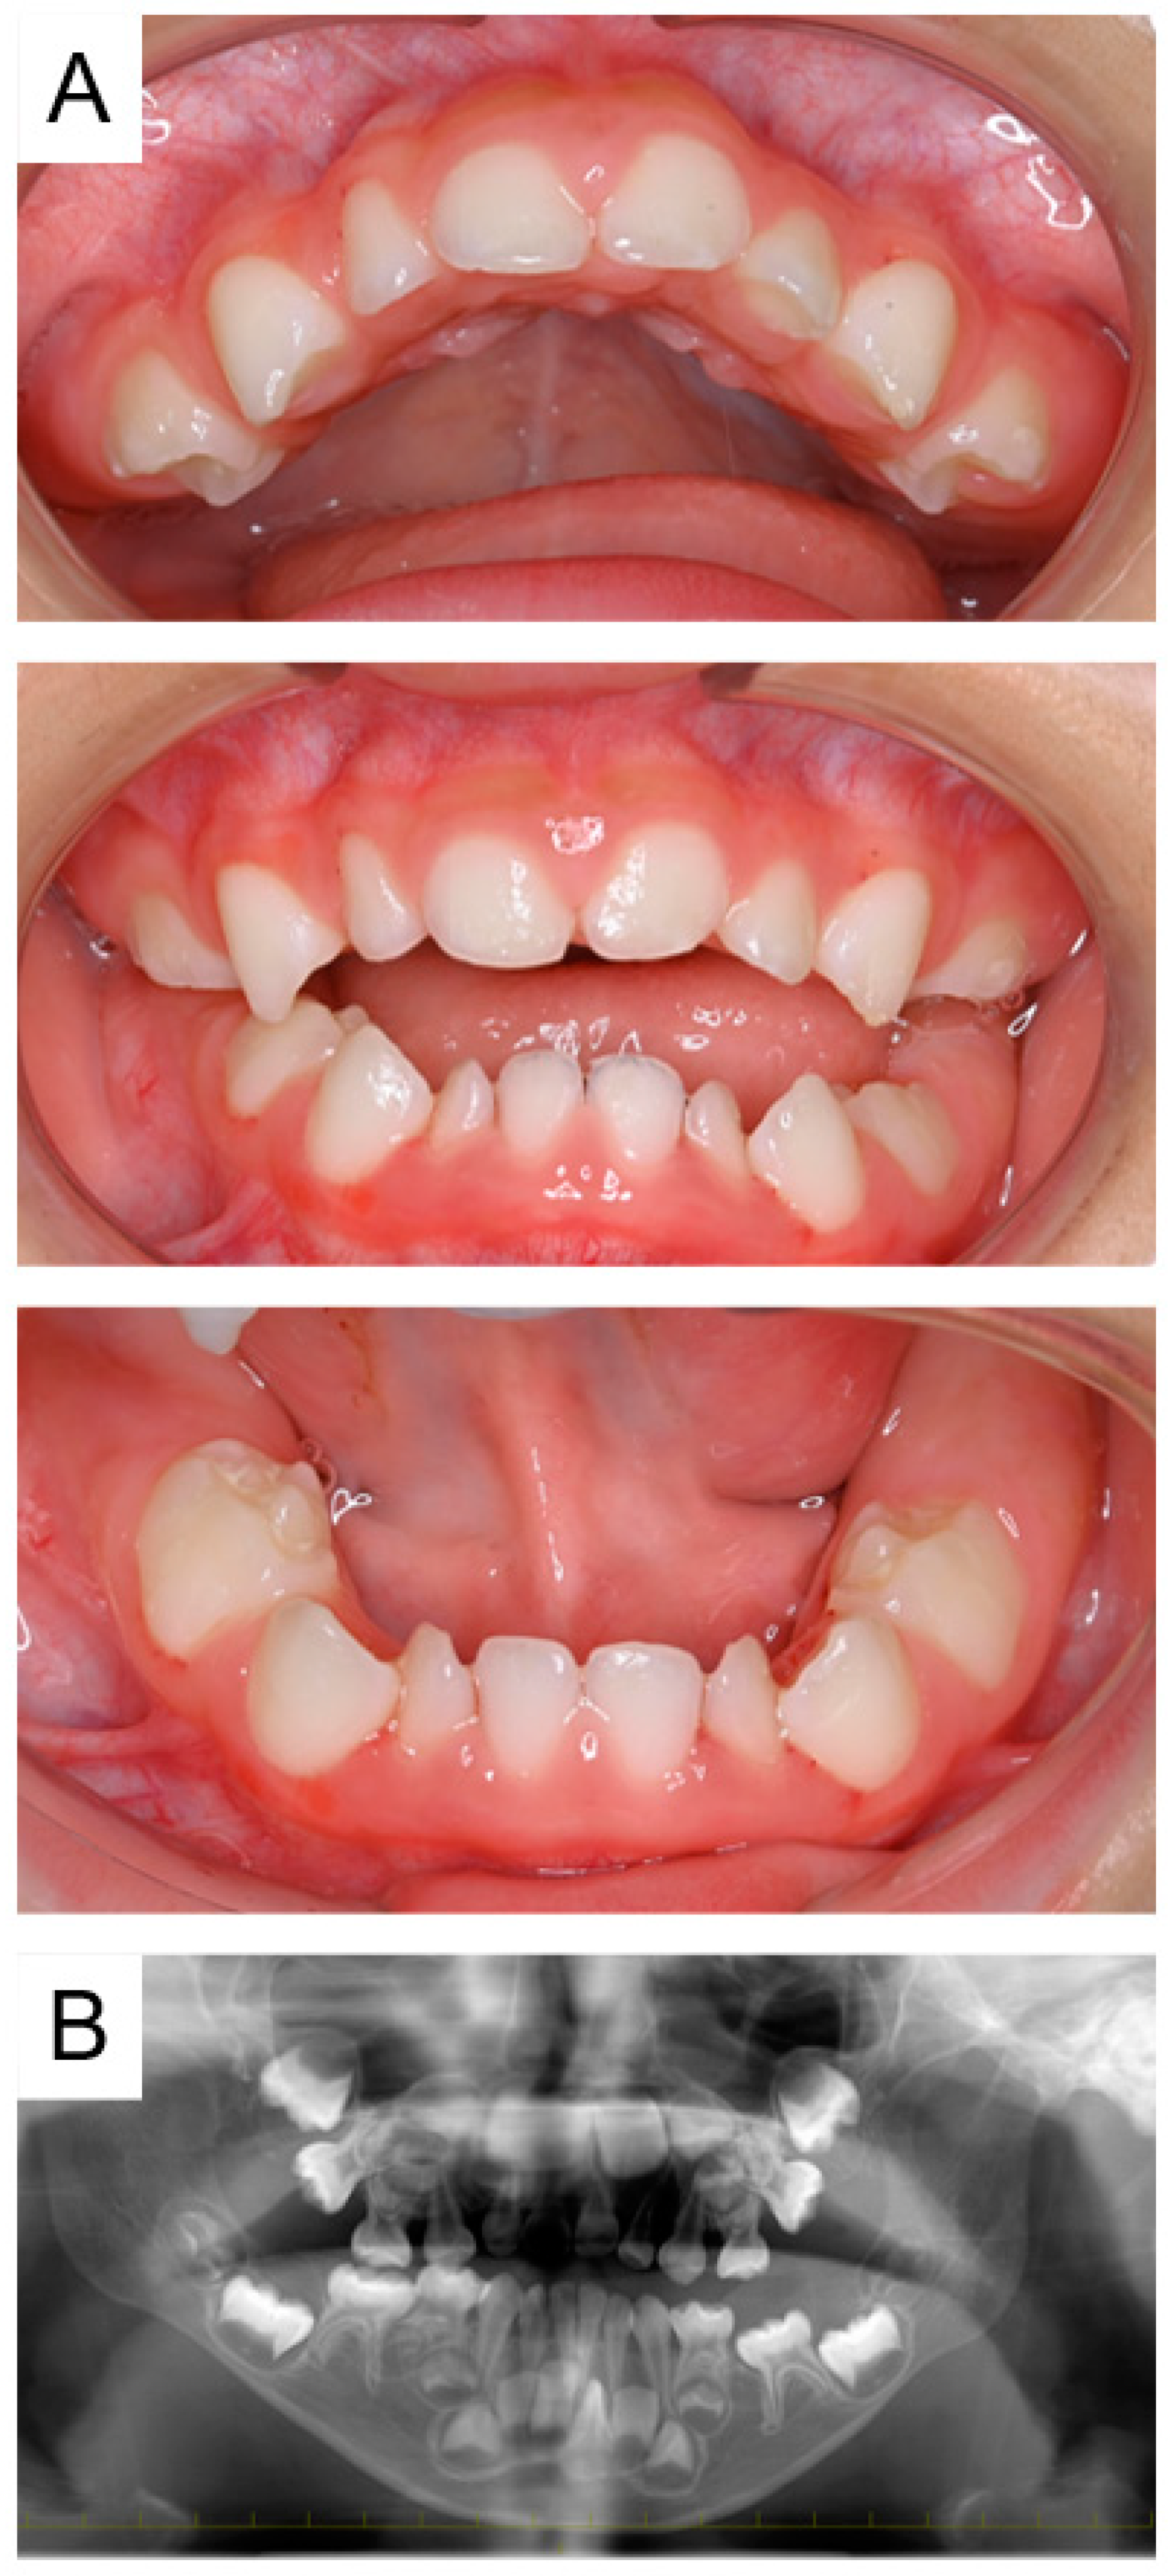

2.1. Case 1

2.2. Case 2